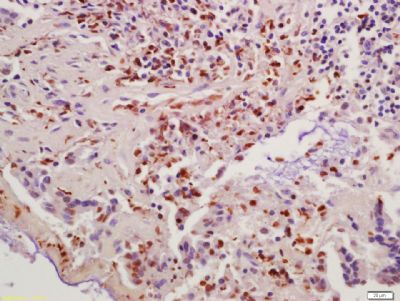

| 产品图片 | ![]() Sample: U937 Cell (Human) Lysate at 30 ug Primary: Anti- Cyclin B1 (bs-0572R) at 1/300 dilution Secondary: IRDye800CW Goat Anti-Rabbit IgG at 1/20000 dilution Predicted band size: 48 kD Observed band size: 50 kD ![]() Sample: U251 Cell (Human) Lysate at 30 ug Primary: Anti- Cyclin B1 (bs-0572R) at 1/300 dilution Secondary: IRDye800CW Goat Anti-Rabbit IgG at 1/20000 dilution Predicted band size: 48 kD Observed band size: 50 kD ![]() Sample: Hela Cell (Human) Lysate at 30 ug Primary: Anti- Cyclin B1 (bs-0572R) at 1/300 dilution Secondary: IRDye800CW Goat Anti-Rabbit IgG at 1/20000 dilution Predicted band size: 48 kD Observed band size: 50 kD ![]() Sample: K562 Cell (Human) Lysate at 30 ug Primary: Anti- Cyclin B1 (bs-0572R) at 1/300 dilution Secondary: IRDye800CW Goat Anti-Rabbit IgG at 1/20000 dilution Predicted band size: 48 kD Observed band size: 50 kD ![]() Paraformaldehyde-fixed, paraffin embedded (Mouse small intestine); Antigen retrieval by boiling in sodium citrate buffer (pH6.0) for 15min; Block endogenous peroxidase by 3% hydrogen peroxide for 20 minutes; Blocking buffer (normal goat serum) at 37°C for 30min; Antibody incubation with (Cyclin B1) Polyclonal Antibody, Unconjugated (bs-0572R) at 1:400 overnight at 4°C, followed by operating according to SP Kit(Rabbit) (sp-0023) instructionsand DAB staining. ![]() Paraformaldehyde-fixed, paraffin embedded (Rat esophageal); Antigen retrieval by boiling in sodium citrate buffer (pH6.0) for 15min; Block endogenous peroxidase by 3% hydrogen peroxide for 20 minutes; Blocking buffer (normal goat serum) at 37°C for 30min; Antibody incubation with (Cyclin B1) Polyclonal Antibody, Unconjugated (bs-0572R) at 1:400 overnight at 4°C, followed by operating according to SP Kit(Rabbit) (sp-0023) instructionsand DAB staining. ![]() Tissue/cell: mouse embryo tissue; 4% Paraformaldehyde-fixed and paraffin-embedded; Antigen retrieval: citrate buffer ( 0.01M, pH 6.0 ), Boiling bathing for 15min; Block endogenous peroxidase by 3% Hydrogen peroxide for 30min; Blocking buffer (normal goat serum,C-0005) at 37℃ for 20 min; Incubation: Anti-Cyclin B1 Polyclonal Antibody, Unconjugated(bs-0572R) 1:500, overnight at 4°C, followed by conjugation to the secondary antibody(SP-0023) and DAB(C-0010) staining ![]() Tissue/cell: human colon carcinoma; 4% Paraformaldehyde-fixed and paraffin-embedded; Antigen retrieval: citrate buffer ( 0.01M, pH 6.0 ), Boiling bathing for 15min; Block endogenous peroxidase by 3% Hydrogen peroxide for 30min; Blocking buffer (normal goat serum,C-0005) at 37℃ for 20 min; Incubation: Anti-Cyclin B1 Polyclonal Antibody, Unconjugated(bs-0572R) 1:200, overnight at 4°C, followed by conjugation to the secondary antibody(SP-0023) and DAB(C-0010) staining ![]() Blank control (blue line): A549 (blue). Primary Antibody (green line): Rabbit Anti-Cyclin B1 antibody(bs-0572R). Dilution: 1μg /10^6 cells; Isotype Control Antibody (orange line): Rabbit IgG . Secondary Antibody (white blue line): F(ab’)2 fragment goat anti-rabbit IgG-FITC. Dilution: 1μg /test. Protocol The cells were fixed with 2% paraformaldehyde (10 min) and then permeabilized with 0.1% PBS-Tween for 20 min at room temperature.Cells stained with Primary Antibody for 30 min at room temperature. The cells were then incubated in 1 X PBS/2%BSA/10% goat serum to block non-specific protein-protein interactions followed by the antibody for 15 min at room temperature. The secondary antibody used for 40 min at room temperature. Acquisition of 20,000 events was performed. ![]() Cell: Hela Concentration:1:100 Host/Isotype:Rabbit/IgG Flow cytometric analysis of primary antibody (Cat#: bs-0572R) on Hela(green) compared with isotype control in the absence of primary antibody (blue) followed by Alexa Fluor 488-conjugated goat anti-rabbit IgG(H+L) secondary antibody . |